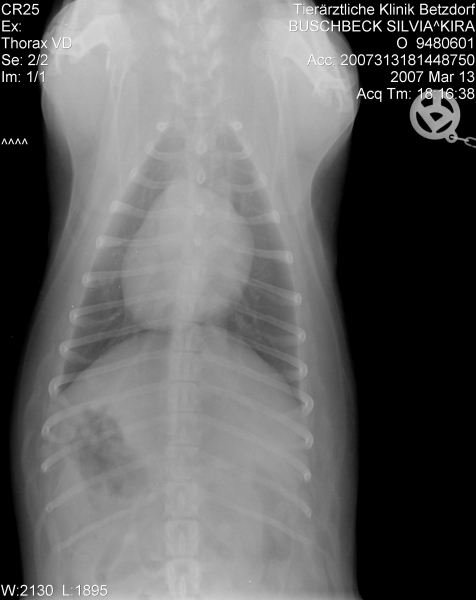

Da Kira aber inzwischen beim TA fürchterlich unter Stress steht, hat man beschlossen, zumindest schon einmal die Röntgenaufnahme des Herzens zu machen.

Die Aufnahme gefiel dem Chef nun weniger und er hat es möglich gemacht, dass Kira gestern abend dann doch noch die Ultraschalluntersuchung bekam.

Kira's Herz ist sehr vergrößert Konfus .

Zum Vergleich: ein normales Herz liegt auf ca. 2 Brustwirbeln auf, Kira's Herz beansprucht 4,5 Brustwirbel und drückt bereits die Luftröhre nach oben Geschockt

Eine Mitralklappeninsuffiziens (geringgradig), eine Pulmonalklappeninsuffizienz (ebenfalls geringgradig) und laut Diagnosebericht für meinen TA eine beginnende HCM. Hier muß ich noch einmal nachfragen, was genau damit gemeint ist.

Die Werte des Herzens sind ansonsten in Ordnung, Durchblutung, Durchflußgeschwindigkeit und Kontraktionen sind alle im Normbereich.

Sie bekommt vorerst keinerlei Medikamente fürs Herz, lediglich ein jährlicher großer CheckUp mit Herzdiagnostik wird künftig gemacht.

Die "undichten" Klappen können - müssen aber nicht - irgendwann einmal Probleme verursachen - im Augenblick tun sie es nicht.

@Christa: Ja, der Doc sagt auch, dass ein ETWAS vergrößertes Herz durchaus die Regel sei. Ihres aber ist fast doppelt so groß wie normal und zeigt zudem eine dicke Herzmuskelwand - eben die beginnende HCM. Zudem ist das Herz ja einseitig noch mal etwas vergrößert, also ungleichmäßig. Was daraus wird....man wird sehen.